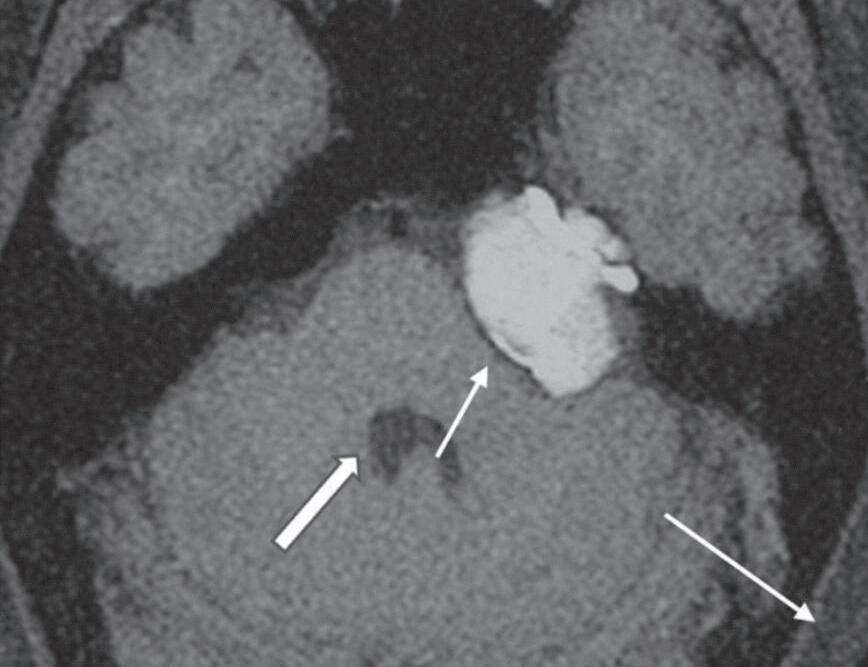

Fig. 1-16. Granuloma de colesterol no ápice petroso: RNM sequência axial T1 (a): lesão expansiva no ápice petroso, comprimindo a ponte, compatível com granuloma de colesterol, com sinal hiperintenso na sequência T1 (seta curta); liquor com sinal hipointenso (seta branca larga); gordura subcutânea com sinal hiperintenso na sequência T1 (seta preta longa). RNM sequência axial T1 com supressão de gordura; (b): a lesão persiste com sinal hiperintenso na sequência T1 com supressão de gordura (seta); liquor no quarto ventrículo com sinal hipointenso (seta larga); gordura subcutânea suprimida. RNM axial T1 com subtração das sequências pré e pós-gadolínio; (c): demonstra apenas áreas de impregnação pelo agente paramagnético, na periferia do granuloma de colesterol (seta). RNM axial T2; (d): lesão expansiva no ápice petroso com depósito periférico de hemossiderina, halo de sinal hipointenso (seta curta); liquor com sinal hiperintenso no quarto ventrículo (seta longa).